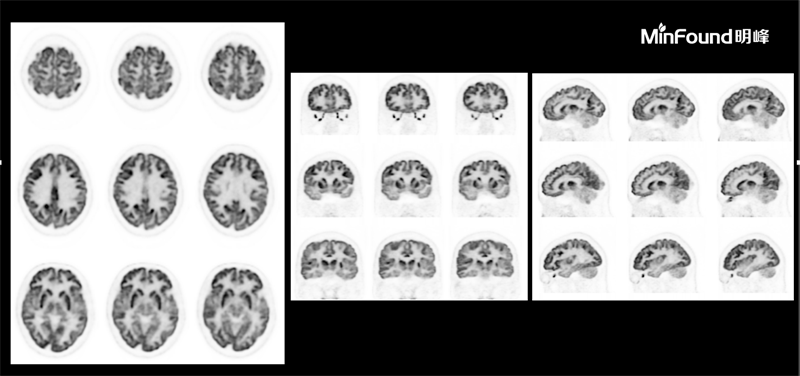

ScintCare PET/CT 730T

ScintCare PET/CT 730T employs a 4th-generation PET detector where lutetium-yttrium oxyorthosilicate (LYSO) crystals are individually coupled to SiPM detectors without the optical conductor (1: 1 coupling and 100% coverage). The digital SiPM detector considerably minimizes photon loss, resulting in improved time resolution (380 ps), system sensitivity (23.5 cps / kBq), and image uniformity, ultimately resulting in high-resolution images under well-curated radiation dose control.

臨床畫(huà)廊